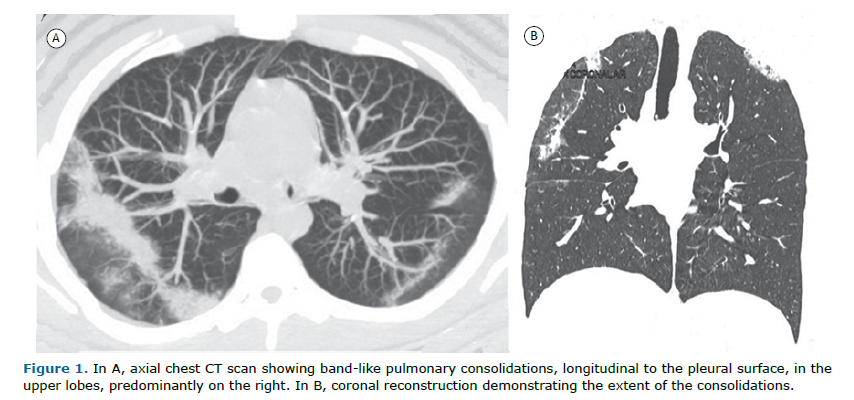

A 21-year-old man complained of a dry cough, progressive dyspnea, and fever for two months. He had peripheral eosinophilia of 1,800/mm3 (27%). A CT scan showed peripheral longitudinal bands of consolidation in the upper lobes (Figure 1). The final diagnosis was chronic eosinophilic pneumonia (CEP).

Most patients with CEP have a history of asthma or atopy. It is characterized by respiratory symptoms for 2 to 4 weeks, diffuse pulmonary alveolar consolidation with air bronchogram and/or ground-glass opacities, eosinophilia in BALF (≥ 40% eosinophils) or eosinophilia in peripheral blood (≥ 1,000/mm³), and absence of other known causes of eosinophilic pneumonia. Symptoms may persist for more than one month and include cough, fever, night sweats, progressive dyspnea, malaise, and weight loss. Blood eosinophilia is present in 90% of patients, and sputum eosinophilia in 50%. Imaging studies may show linear, band-like opacities parallel to the pleural surface. The combination of this imaging finding, the presence of eosinophilia, and response to steroid treatment are usually sufficient for diagnosis, obviating the need for lung biopsy.(1,2)